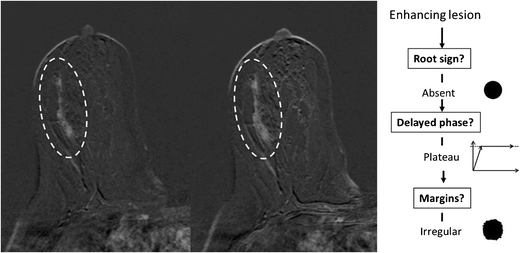

Example of a non-mass lesion: ductal carcinoma in situ (DCIS) Grade 3, presenting as a non-mass lesion without the root sign, with plateau enhancement during the delayed phase and with irregular margins. Based on the Tree flowchart (Fig. 1), the described characteristics resulted in a node 5 rating where malignancy cannot be ruled out